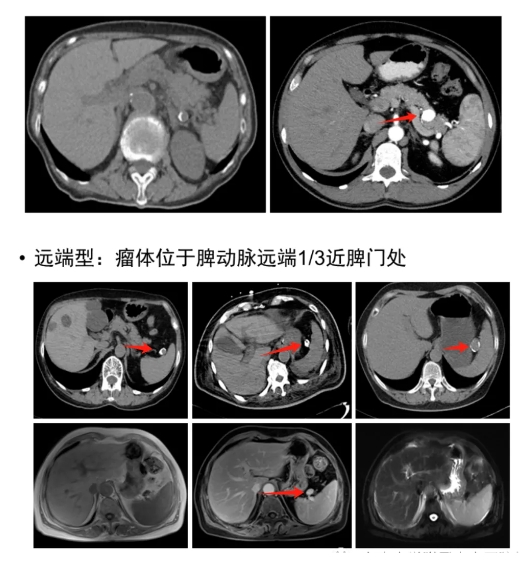

(1)脾动脉瘤未破裂影像学表现

(2)脾动脉瘤破裂时影像学表现